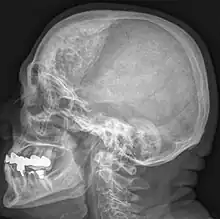

| Hyperostosis frontalis interna in a 74-year-old woman | |

Katz syndrome is a rare congenital disorder, presenting as a polymalformative syndrome characterized by enlarged viscera, hepatomegaly, diabetes, and skeletal anomalies that result in a short stature, cranial hyperostosis, and typical facial features. It is probably a variant of the autosomal recessive type of Craniometaphyseal Dysplasia.[1]